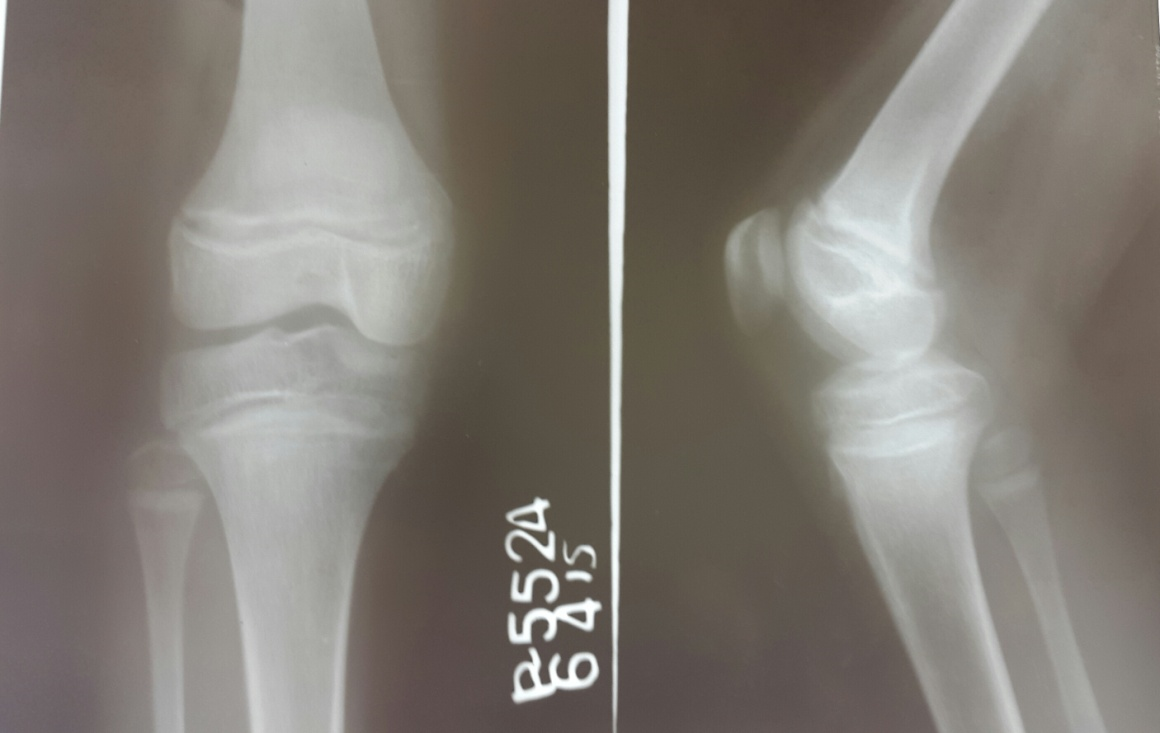

Case 1: An 11 years old girl born of non-consanguineous marriage presented with 3-4 episodes of carpopedal spasms in last 14 days. The dietary (2500kcal/28gms of protein) intake was adequate. Clinical examination revealed height of 140cm (10-25 percentile), weight of 31kgs (10-25 percentile). General and systemic examination was normal. Chovstek sign (fig 1) was positive with carpopedal spasm involving hand and feet. Investigations showed normal hemogram, urine examination and thyroid function tests. Other metabolic work-up is depicted in table 1. Electrocardiogram (ECG) showed long QTc of 0.47sec (fig 2). X-ray Knee joint shows haziness and irregularity at metaphyseal end (Fig 3). Chest X-ray was normal. She was thus diagnosed as hypocalcemic tetany with Vitamin D deficiency. She was started on IV calcium gluconate (5ml in 10ml normal saline slowly over 30 min under cardiac monitor). Subsequently she was treated with vitamin D supplements of cholecalciferol (60000U weekly for 4weeks then monthly for 3 months) along with calcium and phosphate supplements. She was asked to follow up regularly.

Fig 3: X-rays of the knee showing haziness and irregularity at metaphyseal end